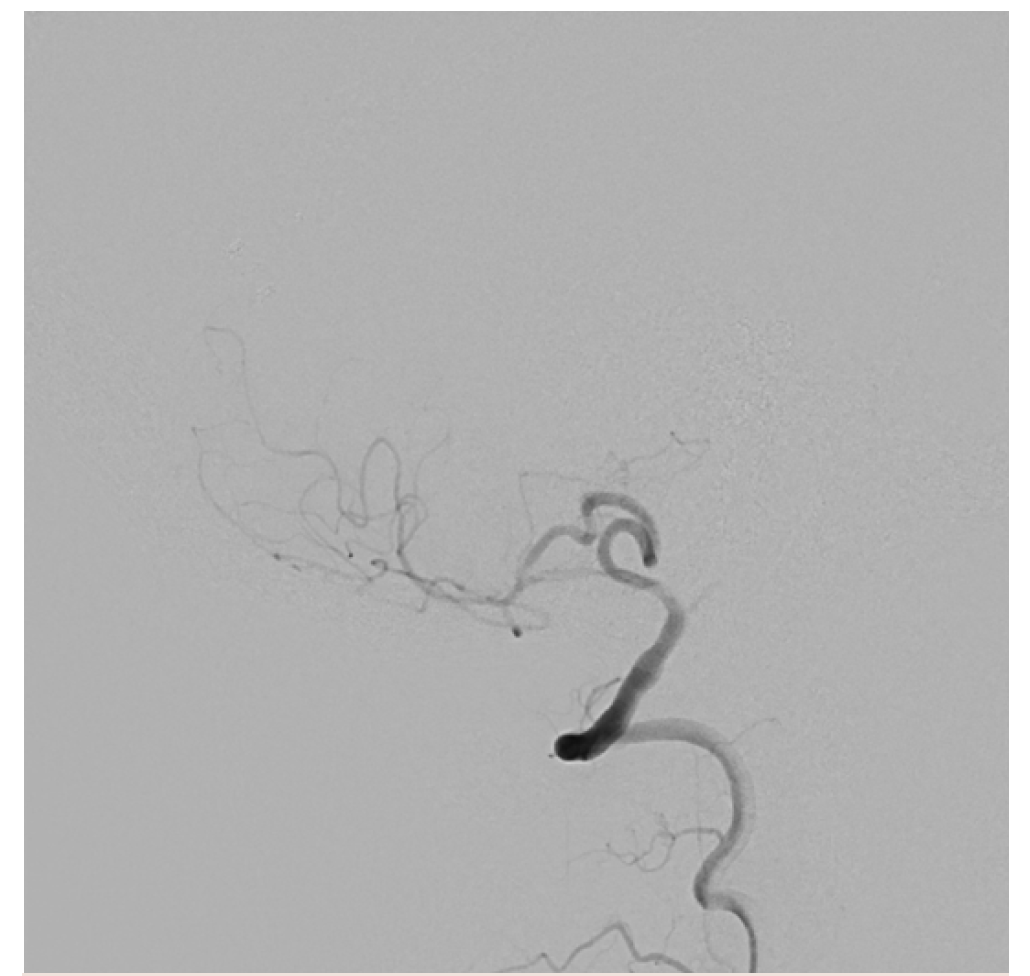

Access was quickly obtained using an Aristotle 18 guidewire (Scientia Vascular) (Figure 13). This is the lowest radiation roadmap setting. Note the outstanding visualization of the catheters and wires. In a long, complex, high-risk case, excellent visualization and radiation sparing are 2 major priorities. The ARTIS icono enables both.

The first pipeline stent was aligned tip-to-tip and ready for deployment (Figure 14). Stent visualization is another major strength of the ARTIS icono. If the DSA roadmap feature is utilized, making a roadmap from a frame of an arteriographic run, then switching to a higher-radiation roadmap setting is an option at this point.